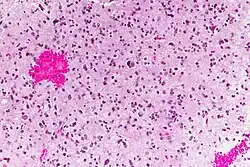

En las imágenes de RM se muestra como una lesión sólida expansiva, mal delimitada, con edema perilesional asociado y que capta contraste. Histológicamente se caracteriza por atipias nucleares, aumento de la celularidad y significativa actividad proliferativa. La neoplasia se infiltra de forma difusa en el tejido circundante, sin destruirlo por completo, de manera que las estructuras afectadas aparecen engrosadas.[3]

Los astrocitomas anaplásicos entran en la categoría de gliomas de alto grado (grado III-IV de la OMS), que son gliomas patológicamente indiferenciados que llevan aparejado un mal pronóstico clínico. Pueden surgir de novo o ser el resultado de una progresión maligna de un astrocitoma difuso (grado II OMS).[1] A diferencia del glioblastoma (grado IV OMS), el astrocitoma anaplásico carece de proliferación vascular y necrosis en la evaluación patológica.[7]

Las muestras de biopsia del tumor por lo general muestran una elevada densidad celular, atipias, mitosis y una significativa actividad proliferativa.[3] El origen astrocitario del tumor puede ser determinado mediante la detección de la GFAP con métodos inmunohistoquímicos. En más de la mitad de los tumores pueden detectarse mutaciones de la proteína Tp53 y de la isocitrato deshidrogenasa (IDH).[1]